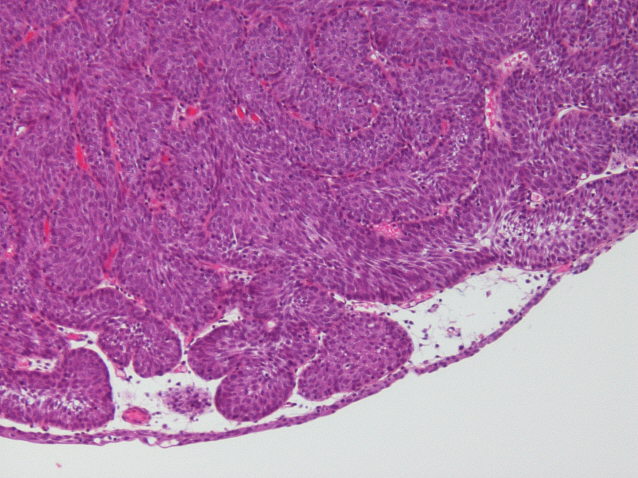

Bladder Papillary Lesions

Case ID: 464